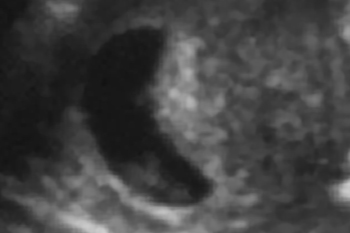

妊娠12週

子宮の中にいる赤ちゃんの超音波写真を見てみましょう。

妊娠中の子宮は、丸くて柔らかく赤ちゃんが心地よく過ごせる場所です。赤ちゃんは本来胎内を、膝を曲げ、指をなめられる姿勢で過ごします。

ところが、子宮まわりの筋肉がコリ固まってカチカチだったり内臓が下がって子宮が押しつぶされたりすると、子宮が細長い形になってしまいます。この中の赤ちゃんは窮屈で楽な姿勢をとることができません。